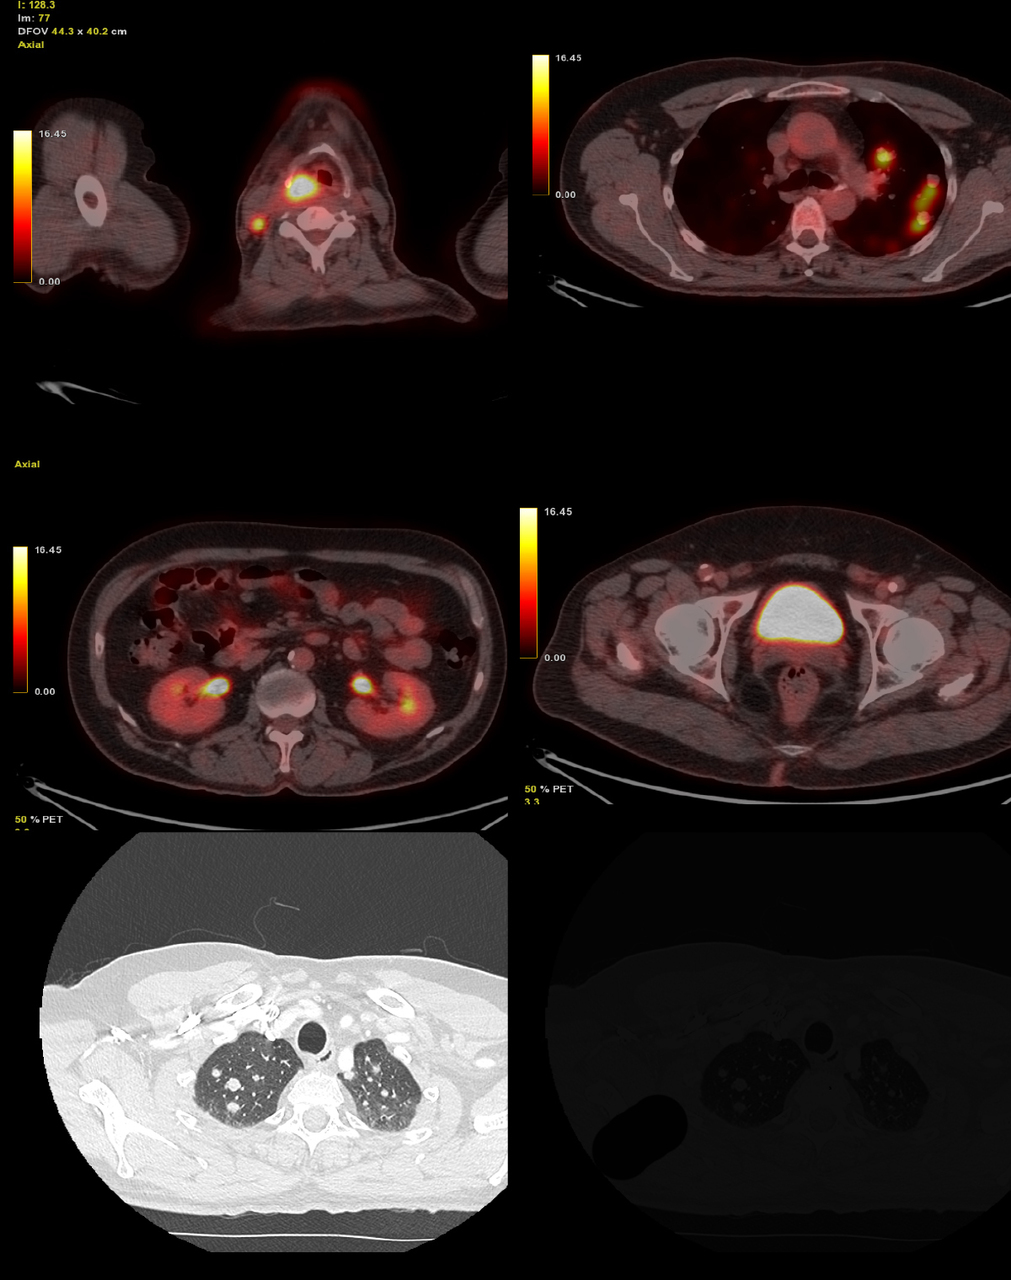

Vous recevez les examens d’imagerie suivants :

Question 8 : Vous visualisez

Hypermétabolisme physiologique (excrétion du marqueur radioactif)

Idem

Calcifications de l’aorte abdominale et des artères fémorales

TEP-scan au 18-FDG avec coupes de scanner thoracique en fenêtre parenchymateuse..

1 : hypermétabolisme pathologique, tumeur de l’hypopharynx droit ;

2 : hypemétabolisme pathologique, adénomagalie tumorale ;

3 : nodule pulmonaire hypermétabolique ;

4 : uretère : hypermétabolisme physiologique, excrétion urinaire du traceur (18-FDG) ;

5 : vessie : hypermétabolisme physiologique, excrétion urinaire du traceur (18-FDG) ;

6 : plaque d’athérome calcifiée ;

7 : nodule pulmonaire

L’examen anatomopathologique de la tumeur de l’hypopharynx droit conclut à un carcinome épidermoïde infiltrant peu différencié non kératinisant.

À propos des nodules pulmonaires, deux hypothèses semblent licites. La première est celle d’un primitif bronchique, l’autre est celle de métastases pulmonaires.